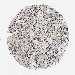

CANCER BREAST CANCER Show tissue menu

BRCA TCGA BRCA VALIDATION PROTEIN EXPRESSION